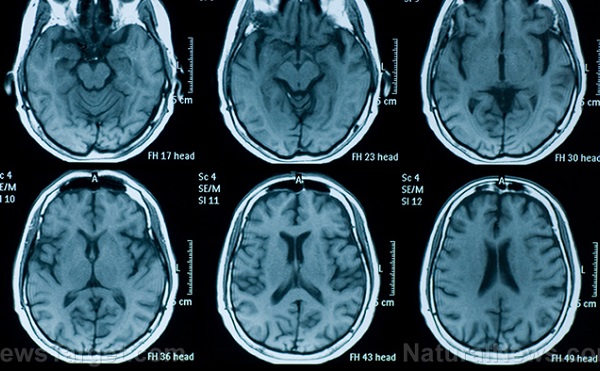

Verseny keretében mérték meg egy mesterséges intelligencián alapuló rendszer tudását: a BioMind 225 esetben, körülbelül 15 perc alatt, 87 százalékos pontossággal állított fel diagnózist, míg 15 tapasztalt orvosból álló csapat csak 66 százalékot ért el.

A Pekingi Tiantan Kórház Neurológiai Kórház Mesterséges Intelligencia Kutatóközpontja és a Capital Medical University kutatócsoportja által kifejlesztett rendszer az agyi hematoma előrejelzésében is 83 százalékos pontosságot ért el. A BioMindba a Tiantan Kórház adatait táplálták, több mint tíz év idegrendszeri megbetegedésekről tárol információt. Ennek köszönhetően a gyakori betegségeket, mint a meningióma és a glioma, 90 százalékos pontossággal diagnosztizálja.

A BioMind 90 százalékos pontossággal diagnosztizálja a gyakori betegségeket